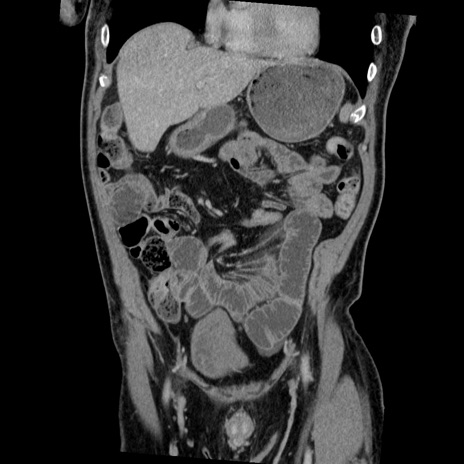

症例22(冠状断像)

【症例】50歳代男性

【主訴】腹痛

【現病歴】AVMからの被殻出血のため回復期リハ病棟入院中。 本日午後3時頃急に下腹部痛が出現した。

【既往歴】AVM、被殻出血、虫垂炎、高血圧

【身体所見】意識晴明、左半身不全麻痺、会話の理解は良好、36.5°C、腹部:膨隆、全体に板状硬、下腹部正中に圧痛点あり、反跳痛-、筋性防御不明、右下腹部にope scar

【データ】WBC 9400、CRP 0.06